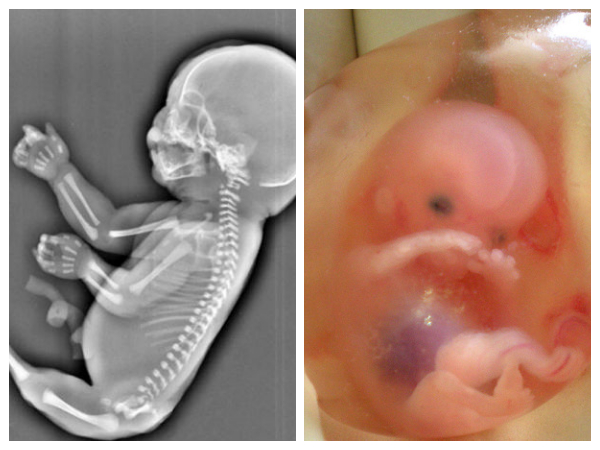

అవును, పెళ్లి చేసుకున్న ఇద్దరు వ్యక్తులు తదుపరి ఈ ప్రపంచంలోకి కొత్త జీవితాన్ని తీసుకురాబోతున్నారు. కానీ ఇప్పుడు చాలా మంది దంపతులు బిడ్డను కనడంలో ఇబ్బందులు ఎదుర్కొంటున్నారు. కానీ బిడ్డకు జన్మనిచ్చిన తర్వాత బాధపడాలని ఏ తల్లిదండ్రులు కోరుకోరు. నిజానికి తమకు పుట్టిన బిడ్డకు చిన్నపాటి నొప్పి కూడా రాకూడదని చాలా మంది అనుకుంటారు. అలాంటప్పుడు, రెండు ప్రత్యేక బ్లడ్ గ్రూపులు ఉన్న తల్లిదండ్రులకు పుట్టిన బిడ్డ జీవితాంతం ఏదో ఒక ఆరోగ్య సమస్యలతో బాధపడుతుందని మీకు తెలుసా? దీన్ని వివరంగా పరిశీలిద్దాం.

Rh నెగిటివ్ తల్లి మరియు Rh పాజిటివ్ తండ్రి నుండి Rh పాజిటివ్ బిడ్డ ఐసోఇమ్యునైజేషన్ అనే ప్రక్రియకు దారి తీస్తుంది. ఇది జరిగినప్పుడు, శిశువు కడుపులో ఉన్నప్పుడే శిశువు రక్తం తల్లి శరీరంలోకి ప్రవేశిస్తుంది. ఇది ప్రసవ తర్వాత సమస్యలకు దారి తీస్తుంది. తల్లి బిడ్డకు అబార్షన్ చేస్తే మరియు Rh పాజిటివ్ తండ్రి రక్తం కలగలిసి ఉంటే ఈ ప్రమాదం సంభవించవచ్చు.

అందుకే Rh నెగిటివ్ తల్లి మరియు Rh పాజిటివ్ తండ్రి ఉన్నవారు Rh పాజిటివ్ బిడ్డను కలిగి ఉండకూడదని వైద్యులు సిఫార్సు చేస్తారు.